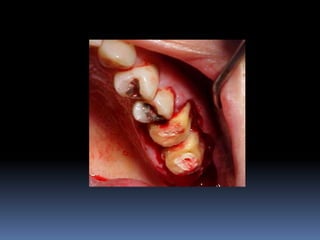

•Necessidades de reabilitações prévias

Dentística, periodontia, cirurgia, prótese, endodontia , ortodontia e DTMs

•Áreas de interesse implantar

Perdas dentárias , tecido ósseo e tecido mucoso